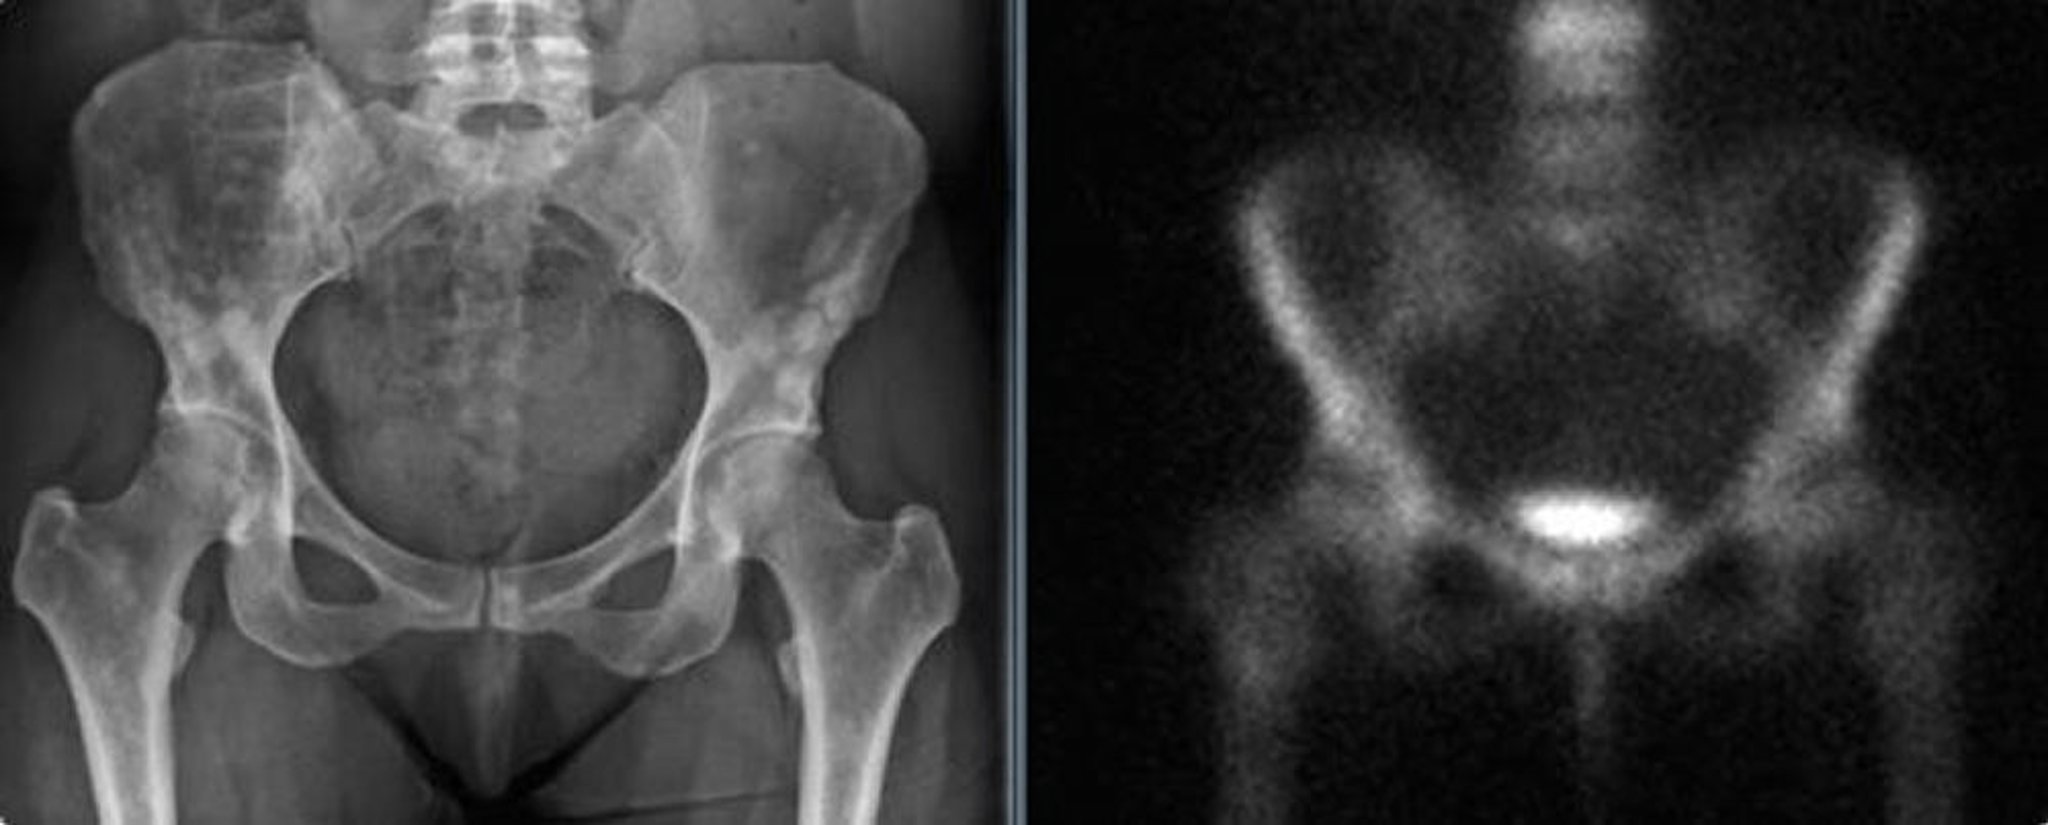

The pelvic radiograph (left) shows osteopoikilosis of the pelvis in an adult woman. These densities could be mistaken for blastic metastases. The bone scan (right) shows no significant increased uptake.

Images courtesy of Michael J. Joyce, MD, and David M. Joyce, MD.